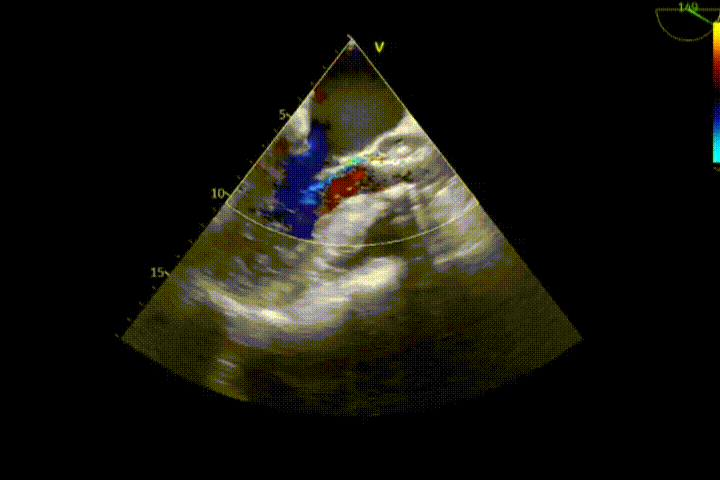

超声心动图提示:主动脉瓣瓣缘明显增厚、钙化、黏连,回声增强,开放受限,为二叶瓣;主动脉瓣上峰值流速:5.76m/s,平均压差:69mmHg;舒张期主动脉瓣下见中量反流;室间隔与左室后壁对称性增厚,TAPSE:28mm。

患者术后即刻食道超声和造影可见支架位置固定良好,支架扩张形态均匀一致,瓣叶启闭运动好。植入主动面瓣膜最大峰值血流速为1.4m/s,平均跨瓣压差为8mmHg,瓣口面积约为2.4cm²,支架内未见明显反流,瓣架前后缘轻度瓣周漏。

术后即刻TEE

术后第4天超声提示人工支架瓣膜位置良好,无移位,瓣膜活动度佳。舒张期主动脉瓣周微量反流。